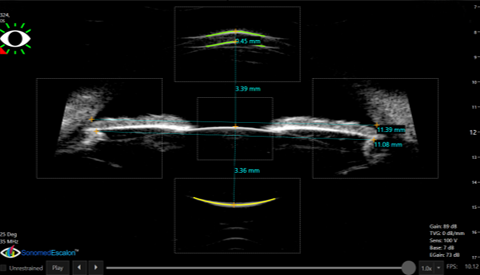

SULCUS-TO-SULCUS

Use of sulcus-to-sulcus measurements obtained by UBM input into well-established nomograms has been used by many leading ICL surgeons to achieve significantly improved sizing reliability vs. the OCOS method based on white-to-white. Align Assist and other tools to ensure well-aligned images are exclusively available in the VuMAX HD and VuPad systems to ensure accurate sulcus-to-sulcus measurements and sizing results.